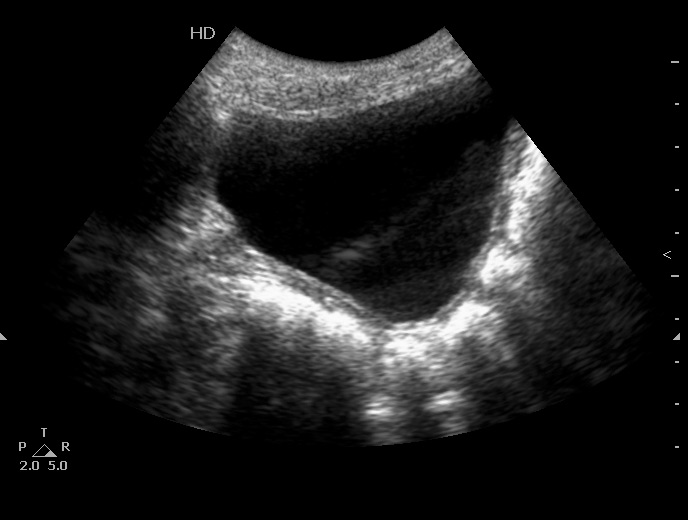

Почки:

Определяется небольшое расширение лоханок обеих почек, стенки их гиперэхогенные, утолщены.

Меня больше всего заинтересовало тканевое образование в нижнем полюсе левой почки - гиперэхогенное, многоузловое. Есть мысли про причину такого состояния почек, но пока хочу выслушать мнения коллег. Буду очень благодарен за отзывы.

Спленомегалии нет. печень без признаков фиброза . Почки уменьшены ( правая - 50 х 20 мм, левая - чуть больше , но за счёт образования нижнего полюса). В левой почке в образовании - есть одиночная небольшая киста ( см клип про почки №3), но на поликистоз непохоже. Ещё одно "но" : с аутосомно - рецессивной поликистозной болезнью почек до 10 лет не живут.

"Маленькие белые почки" с расширением ЧЛС и мочеточников, умеренной латерализацией устьев, без видимых на высокочастотном УЗИ кист. Печень без видимых на высокочастотном УЗИ кист. Опухоль слева.